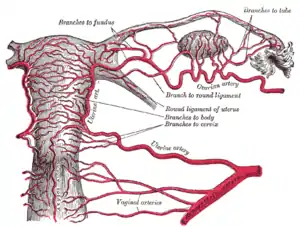

Blood supply

The uterus is supplied by arterial blood both from the uterine artery and the ovarian artery. Another anastomotic branch may also supply the uterus from anastomosis of these two arteries.

Female pelvis and its contents, seen from above and in front The arteries of the internal organs of generation of the female, seen from behind

The arteries of the internal organs of generation of the female, seen from behind Median sagittal section of female pelvis